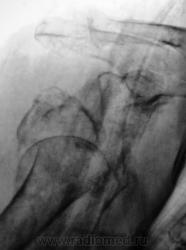

А так было до репозиции - первичный снимок.

Бесформенность между головкой и впадиной - фрагмент плечевой кости. Репозиция никакая.